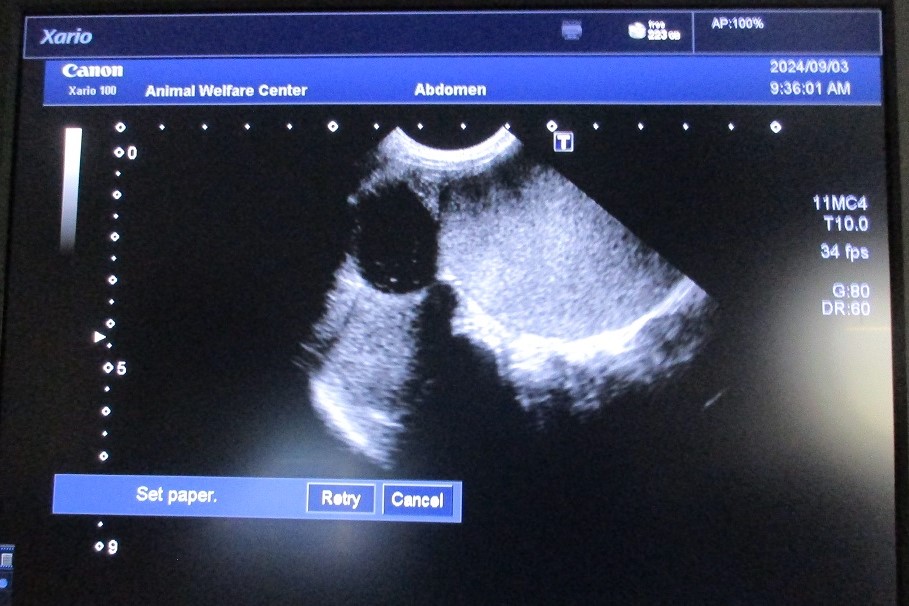

クシャナ 猫・雑種・避妊雌・令和6年7月収容時6歳

- 主訴

- 収容時から右前肢が断脚されており、マンソン裂頭条虫が寄生し、腹囲膨満がありました。

腹部超音波検査により子宮の拡張が疑われました。 - 治療等の内容

- (公社)神奈川県獣医師会の先生に拡張した子宮の摘出を行っていただきました。

- その後

- 症状は落ち着き、令和6年12月に譲渡されました。